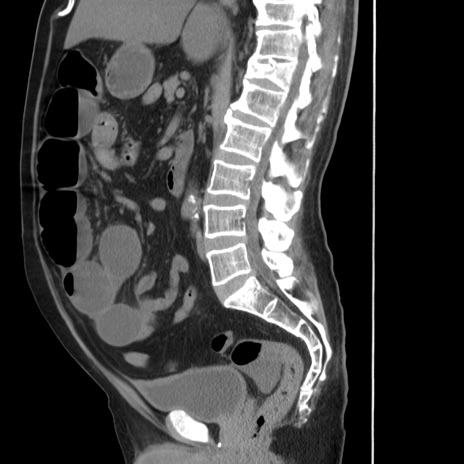

症例20(矢状断像)

【症例】 60歳代男性

【主訴】 腹部膨満、嘔吐

【現病歴】5日前頃より倦怠感を認め食事量減少し4日前の朝嘔吐、食事摂取困難となった。 3日前近医受診し点滴施行され整腸剤などを処方された。 当日他院を受診し、腹部膨満著明、炎症反応の上昇(CRP10.8、WBC11200)あり、紹介受診となる。

【身体所見】 意識JCS1 受け答えがはっきりしないBP 111/57mHg、 P 67bpm、、BT35.2°C、SpO2 97%(RA)、 腹部:膨隆、打診で鼓音あり、全体的に圧痛有り、腸蠕動音(-)、反跳痛ははっきりせず。

【データ】WBC 11400、CRP 14.20